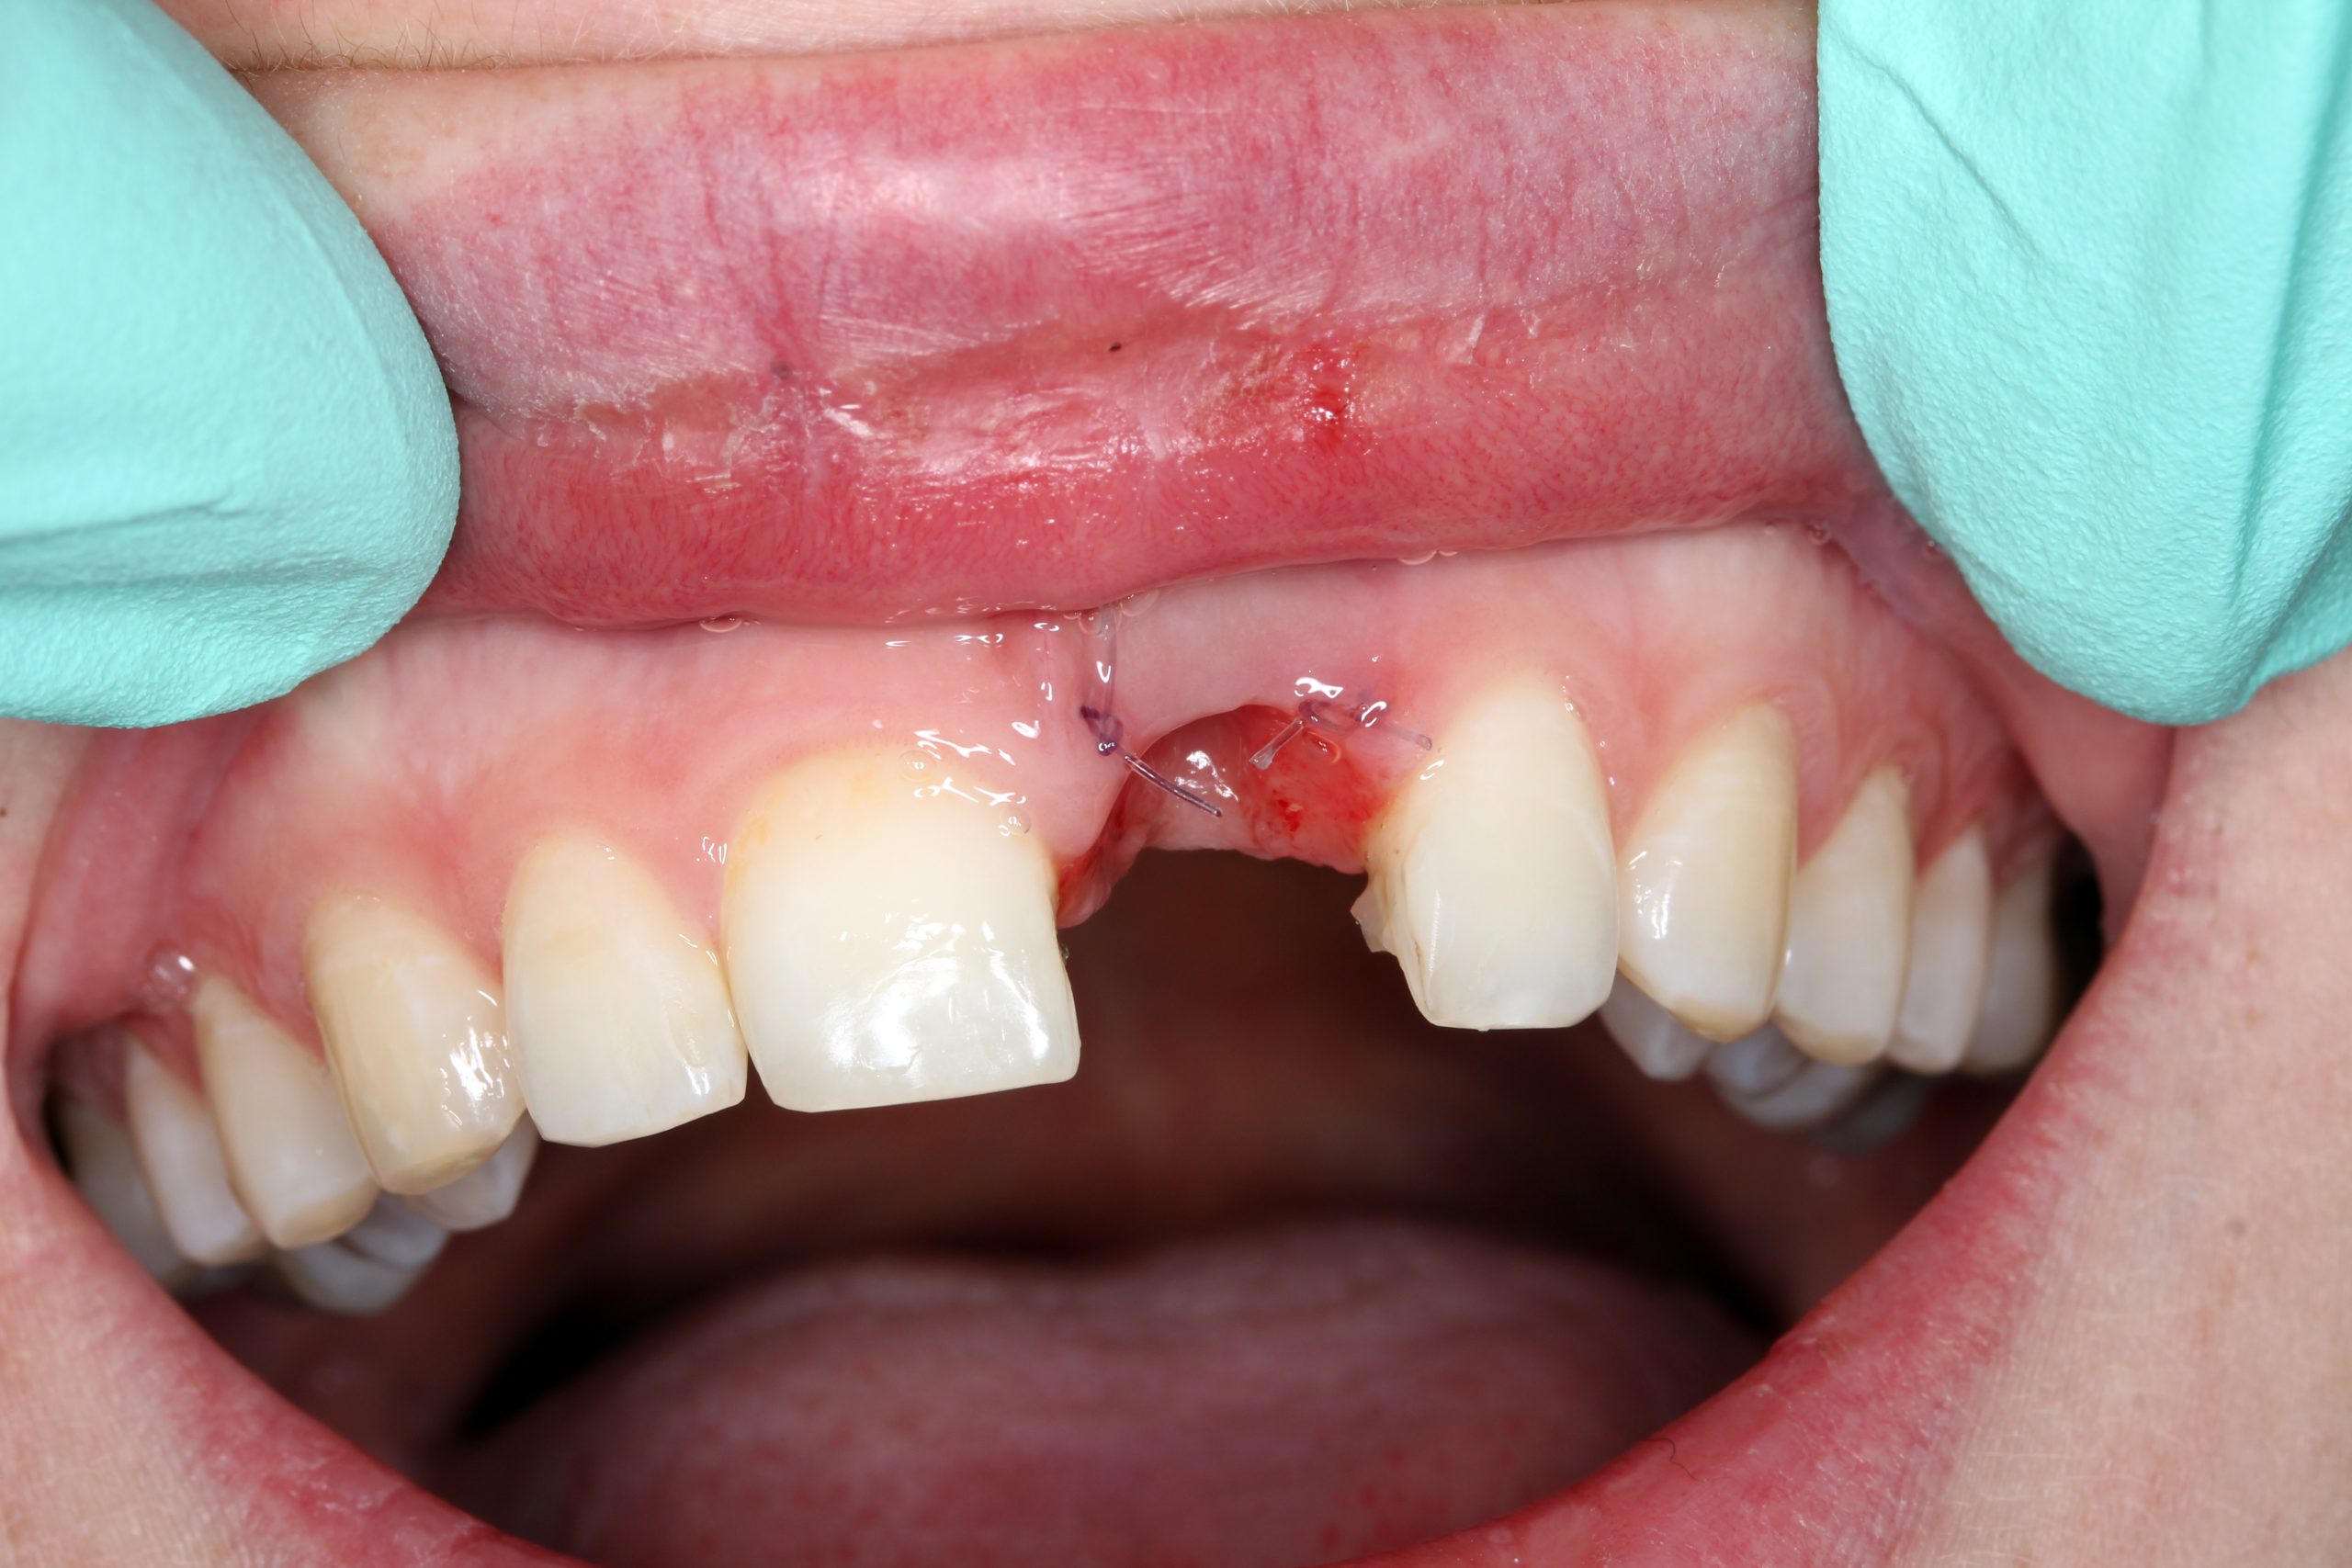

After removal of the crown: a perfectly epithelialized extraction site and preserved interdental papillae. The wire splint with which the dental crown had been temporarily fixed was temporarily retained as a control element for inserting the implant.

The mucoperiosteal flap was lifted palatally and partially mobilized vestibularly. A 14 mm long BioniQ implant from LASAK with Ø 4 mm was inserted and a temporary abutment was attached after removing the implant carrier.